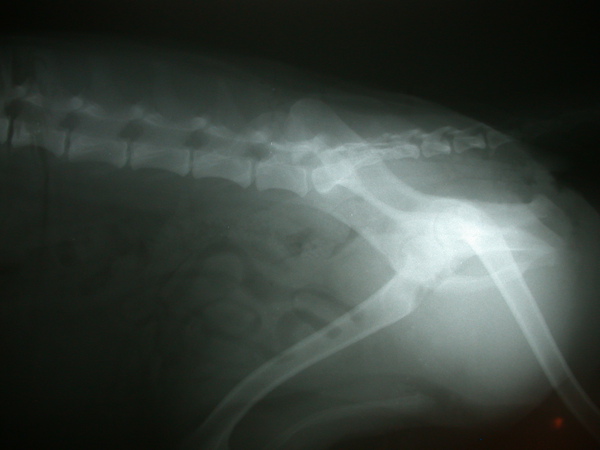

以下是AMO的X光片

兩種都各拍了三張

http://pic.pimg.tw/fishzi/4b8907fbebadb.jpg

http://pic.pimg.tw/fishzi/4b890800d0476.jpg